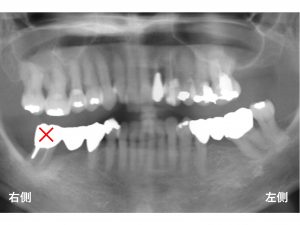

以下が初診時です。

下顎右側の奥歯が腫れて痛い!

噛めないとのことでした。

検査の結果、

下顎左側一番奥歯は、骨の吸収が非常に大きい状態でした。